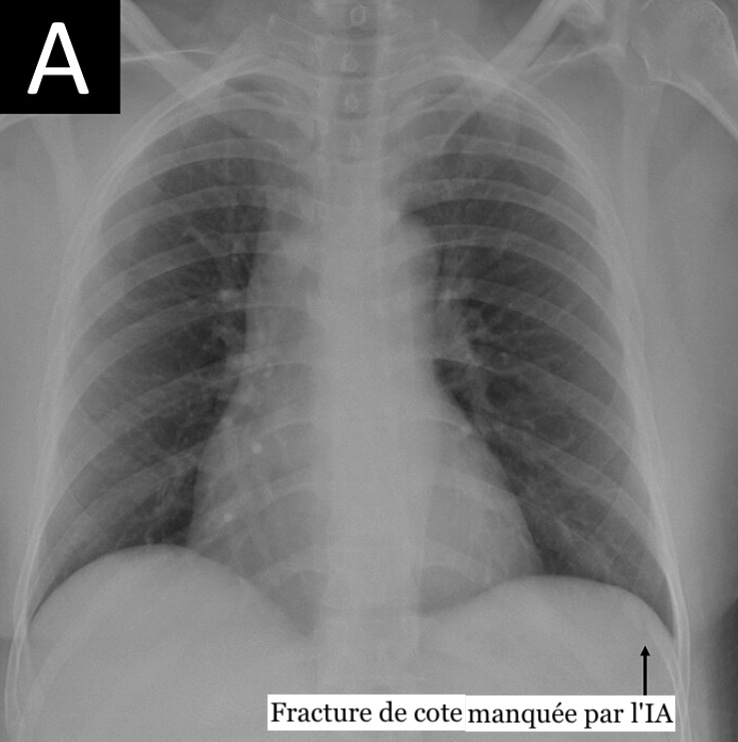

Un outil d'intelligence artificielle (IA) utilisé dans une étude danoise publiée dans la Revue Radiology pour interpréter des radiographies pulmonaires s'est avéré efficace pour exclure une pathologie. Il a présenté des taux d'échec critiques sur les radiographies pulmonaires égaux ou inférieurs à ceux des radiologues, ses erreurs se révélant plus graves cliniquement.

Des chercheurs danois ont initié une étude, publiée dans la Revue Radiology, qui a pour but d'estimer la proportion de radiographies pulmonaires de base où l'IA pourrait exclure correctement une pathologie sans augmenter les erreurs de diagnostic. Ils ont pris en compte des comptes rendus radiologiques et des données images de 1 961 patients (âge médian 72 ans ; 993 femmes), une radiographie pulmonaire ayant été réalisée par patient dans quatre hôpitaux danois.